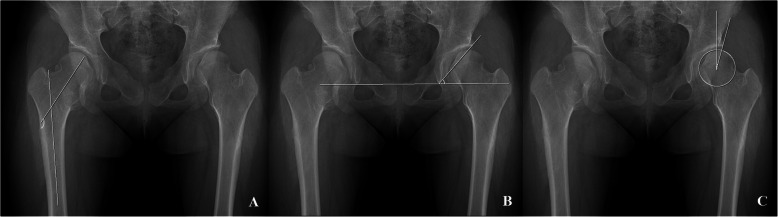

Radiographic analysis was conducted using the last follow-up radiographs in patients who had not undergone any surgical intervention, and the last preoperative radiographs in those who had undergone surgical treatment around the hip joints. For the morphometry of the hip joint in patients with MHE, the femoral neck-shaft angle of Muller [19] was evaluated to assess proximal femur deformity, and Sharp’s acetabular angle [20] and the center-edge (CE) angle [21, 22] were evaluated to assess the deformities of acetabulum (Fig. 2). For FAI evaluation, alpha angle (Fig. 2) of all hips was measured regardless of the presence or absence of symptoms. For IFI evaluation, hip CT studies in patients with MHE were performed in the neutral supine position and the nearest distance between the exostoses and ischium around the lesser trochanter area were measured at axial plane (Fig. 3).

Fig. 2.

Plain radiographic measurements to evaluate the hip joint deformities. a The femoral neck-shaft angle is determined by measuring the angle created by a line in the central axis of femoral shaft and a second line created by the connection of the femoral head center to the mid portion of the femoral head and neck junction contour. b Sharp’s angle is determined by measuring the angle created by a line connecting the acetabular tear drops and a second line connecting a tear drop and the sourcil end. c The center-edge angle is determined by measuring the angle created by a line connecting the vertical line to the tear drop line through the center of the femoral head and a second line from the center of the hip to the lateral acetabular wall margin